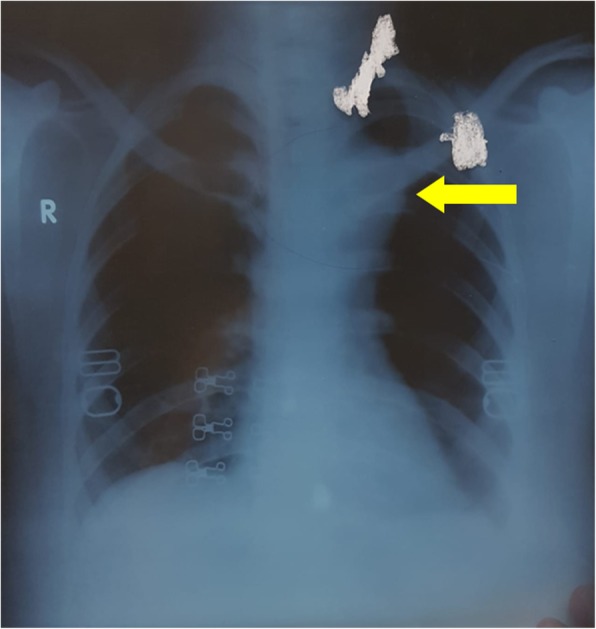

Fig. 1.

Chest Xray PA view showing widened mediastinum (yellow arrow)

A 30 year-old female patient presented with left sided chest pain and intermittent fever and cough for 6 months and massive hemoptysis for a week. There was a history of cerebral venous sinus thrombosis in the sigmoid sinus about 2 years ago for which she received Rivaroxaban. Chest X-ray revealed widened mediastinum (Fig. 1). Upon investigating through CT scan, pseudo-aneurysm of proximal descending thoracic aorta at the level of the left Subclavian artery was found (Fig. 2); the diameter was 83 mm, with a patent lumen of 33 mm. A partially occluding thrombus was also present, as seen in Fig. 3. Consequently the patient was admitted and Internal Medicine team was consulted preoperatively to rule out mycotic aneurysm. Serology including AMA, ANA, VDRL, IgG and IgM were all negative; however an ESR of 90 was obtained.